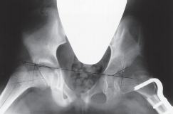

通常由家长发现或体检时发现患儿臀纹不对称,患侧臀部增宽,腹股沟纹理变短,臀纹升高或数量增多,髋关节外展受限,双下肢不等长,学步后摇摆步态等。不同年龄的发育性髋关节发育不良其临床表现存在较大差异,新生儿期进行仔细的临床检查十分重要。医生查体时可发现Ortolani征、Barlow征及Galeazzi征等呈阳性。早期诊断依靠体格检查和超声和髋关节X线检查即可确诊。

临床上辅助检查主要包括超声检查、X线检查、CT、MRI等多种方法。超声检查主要用于4个月以内婴儿,假阳性率高,可动态观察,虽无放射性损害,但检查结果差异性大,对检查者要求高。髋关节X线片检查适合4个月以上的患者,可直观的看出髋关节骨性结构的异常。 CT主要用于大龄儿童CT的三维重建,有利于观察髋关节是否复位。MRI主要用于显示闭合复位或切开复位后股骨头与髋臼之间的匹配情况,尤其能清晰显示软骨和关节盂唇的相关情况,需要镇静。